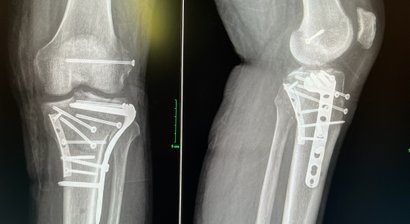

* Behandlung von akuten Tibiakopffrakturen oder deren Folgen

* Therapie von chronischen Schäden am Kniegelenk (Gelenkerhaltende Chirurgie, Osteotomie)

Osteotomie - Beinachsenkorrektur

Sensationelle Herangehensweise an das Problem und die Ursache

Bei der Reha bin ich dann auf Dr. Roider aufmerksam gemacht worden und wie er an mein Problem herangegengen ist, hat mich fasziniert und begeistert.

Er hat die Ursache herausgefunden und mit einer nicht ganz so gängigen Operation/ Doppelete Osteotomie den Grund meiner Schmerzen beseitigt. Seit zwei Monaten bin ich nun Schmerzfrei, ein neues Lebensgefühl und Lebensqualität, die ich durch Dr. Roider zurcückgewonnen habe.